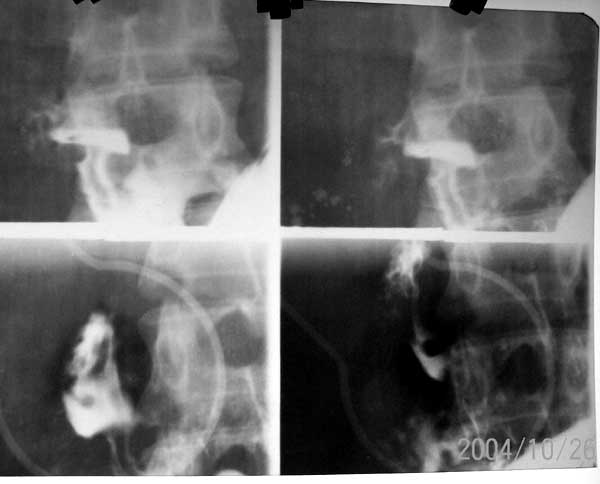

标题: X0127:[讨论]十二指肠球部病变 有结果 [打印本页]

标题: X0127:[讨论]十二指肠球部病变 有结果

考虑息肉,第7幅图像好像可见蒂?不好意思n年没做过胃肠[emb18]

很对不起 抱歉 这是很久以前片子 现无法找到病理结果  当时诊断是 布氏腺增生 仅供参考

球部充盈缺损,有蒂相连。良性点位息肉可能性大。其它就留给胃镜吧

2004/10/26的片子,一般经验,小的称息肉,大得叫腺瘤。

十二指肠布氏腺增生症

这是lihuuuu说的结果

单发布氏腺增生与十二指肠腺瘤发病率都较低 x线鉴别困难

位置形态应该是布氏增生,很罕见.